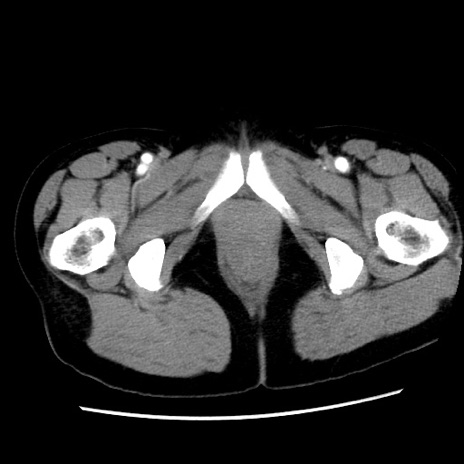

矢状断像

【症例】 50歳代女性

【主訴】 腹痛

【現病歴】前日生レバーを食べた。今朝に排便あり。 昼前に突然発症の腹痛を生じ、当院救急外来を受診した。

【既往歴】 子宮筋腫にてで子宮全摘後

【身体所見】 意識清明、腹部:平坦、軟、下腹部やや左を中心に圧痛・反跳痛あり、筋性防御あり

【データ】WBC 7800、CRP 0.07